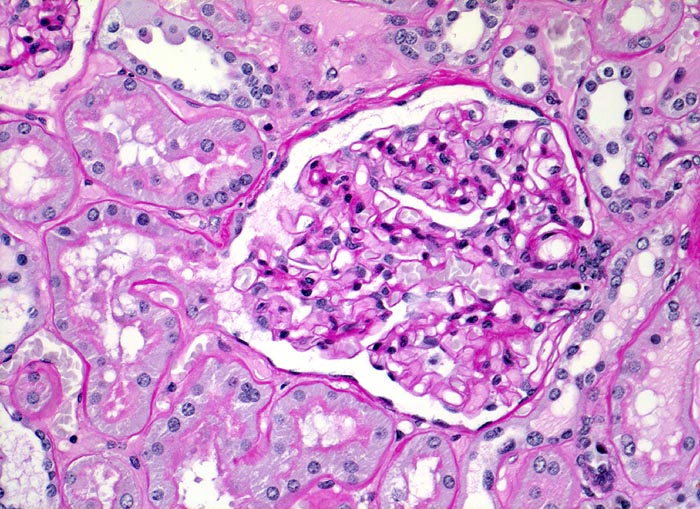

Morphologie:

Akute Infarkte bilden histologisch scharf begrenzte kokardenförmig aufgebaute Herde mit zentraler Koagulationsnekrose umgeben von einem Saum neutrophiler Granulozyten. In der Peripherie ist das partiell geschädigte Gewebe ödematös hämorrhagisch und enthält dilatierte hyperämische Gefässe. Die Nekrose wird durch neutrophile Granulozyten und Makrophagen abgebaut und durch Granulationsgewebe ersetzt, welches zu einer gefässarmen Narbe schrumpft. Die äusserste Rindenzone bleibt infolge der Kollateralversorgung durch Kapselgefässe oft vom Infarkt ausgespart. Infarktnarben können wie alle Narben verkalken.